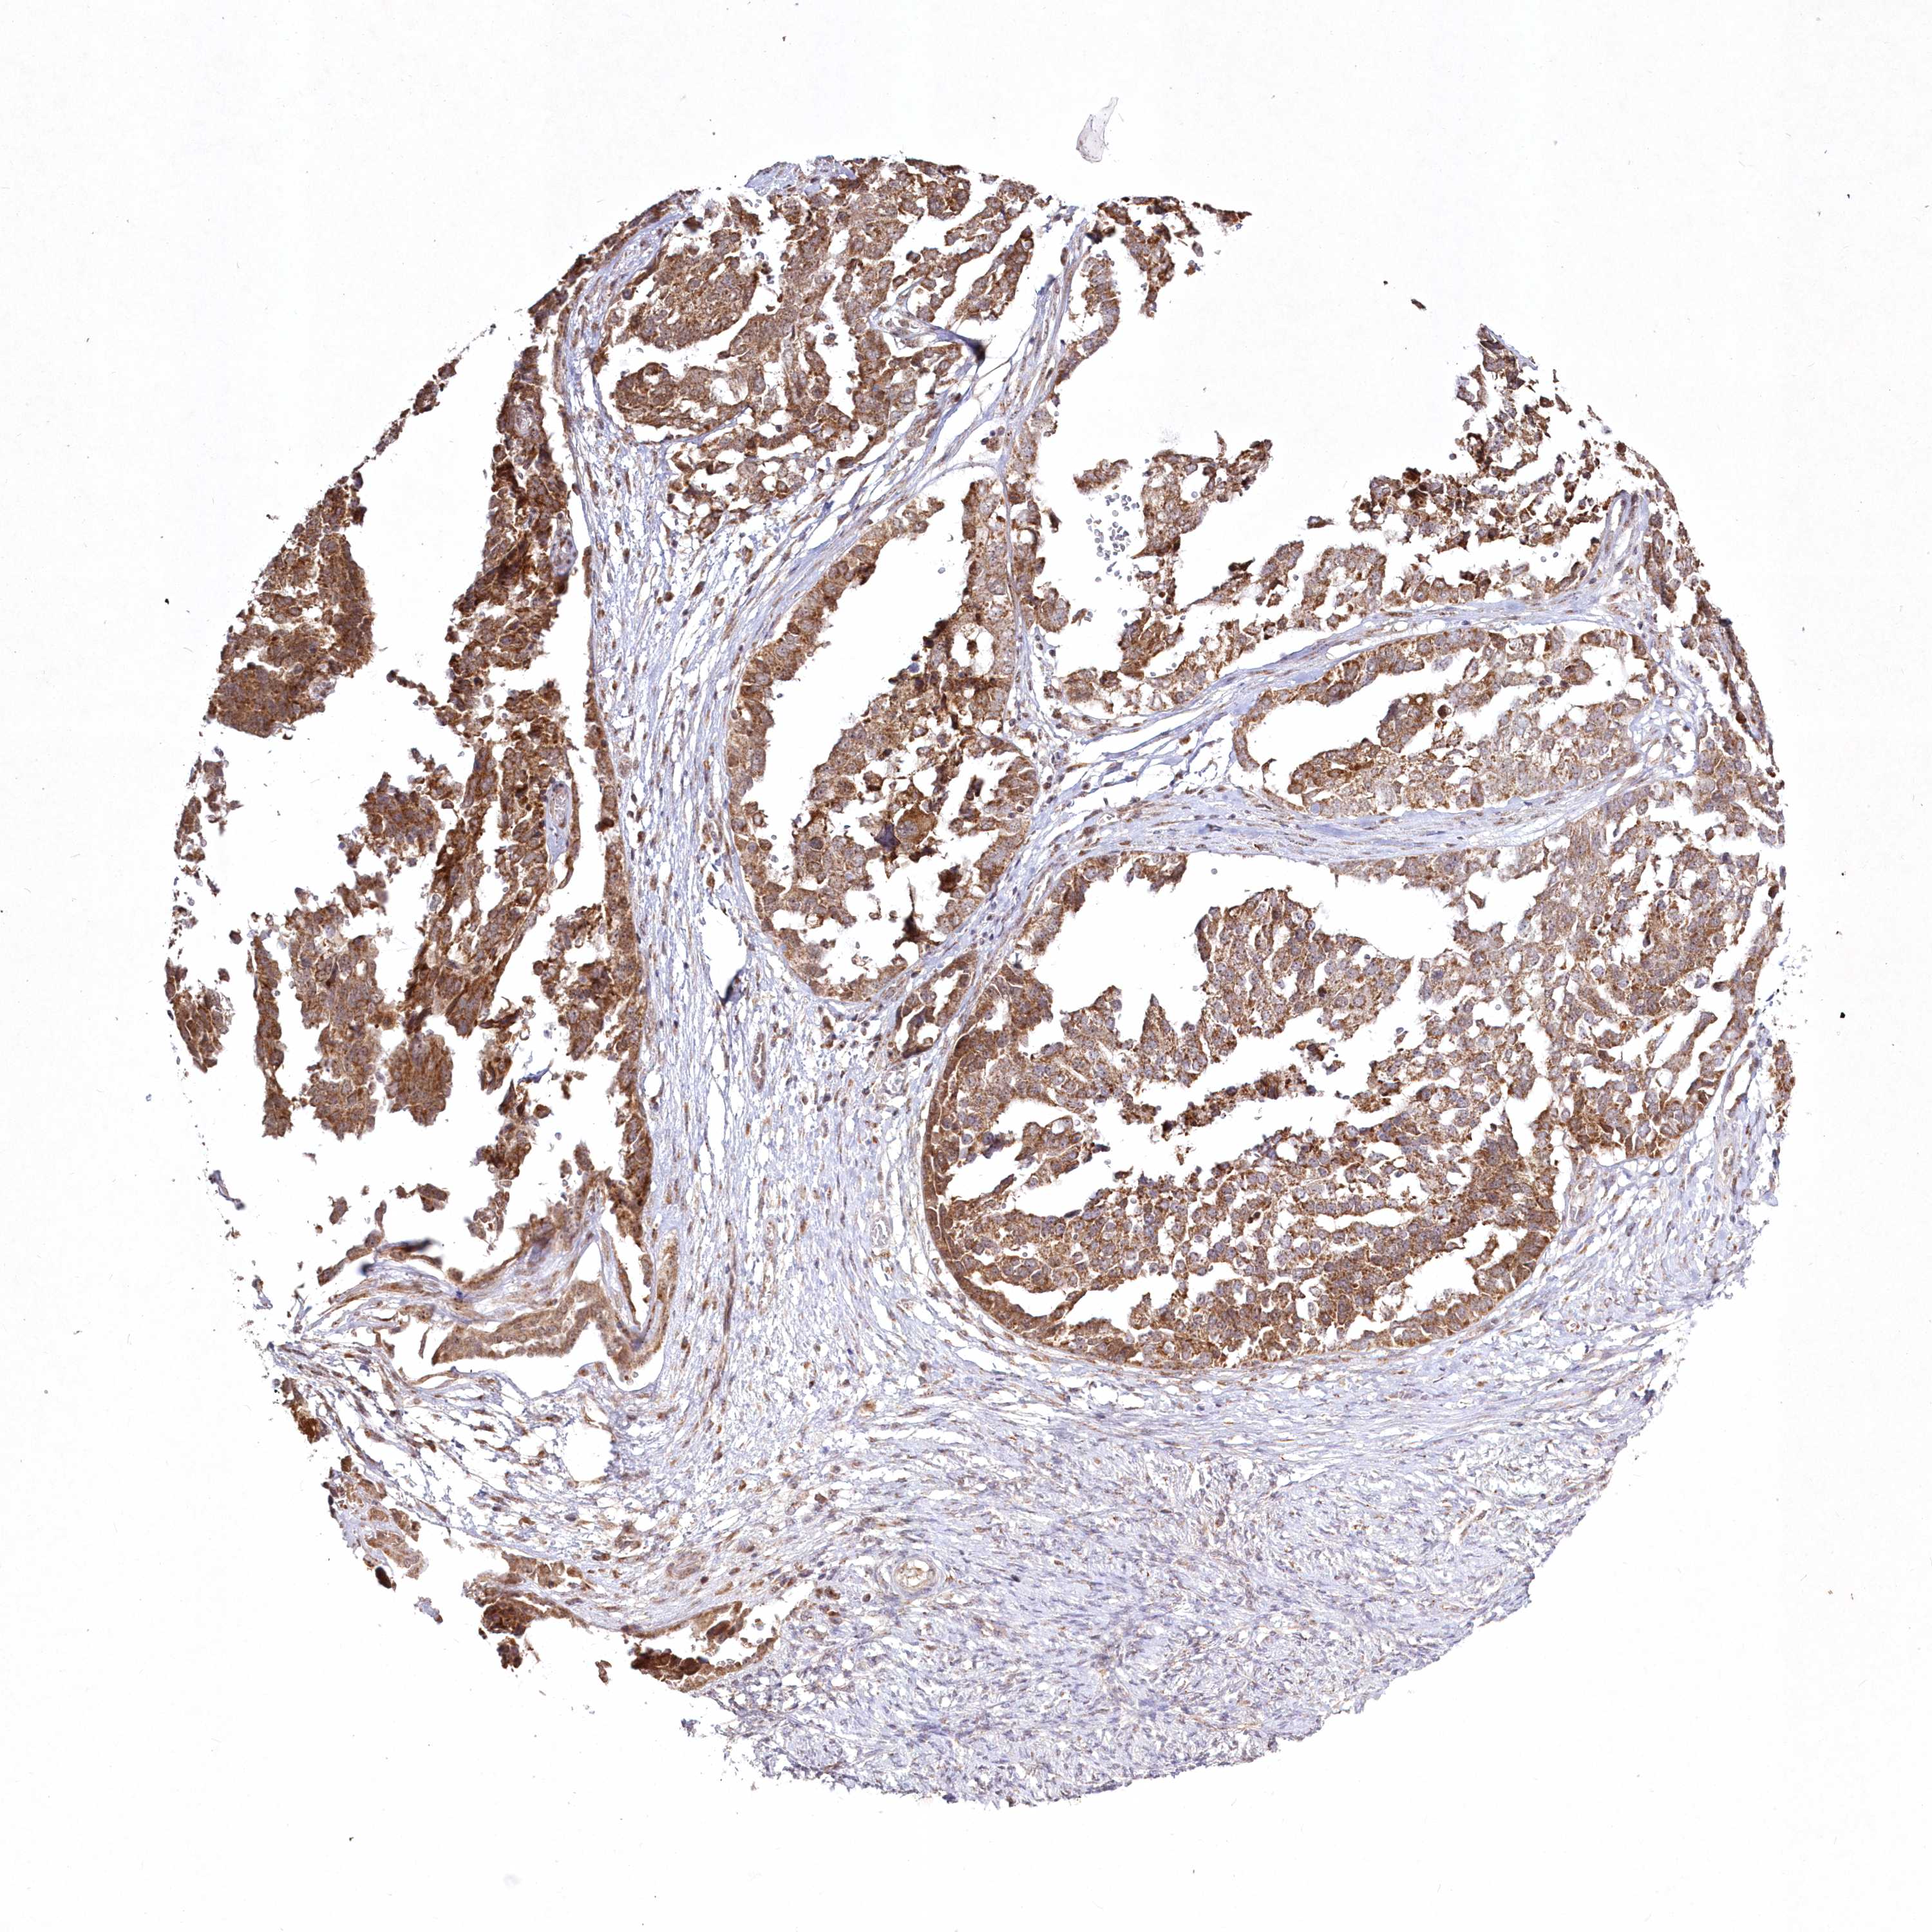

OVARIAN CANCER - Protein expressioni

A mouse-over function shows sample information and annotation data. Click on an image to view it in a full screen mode. Samples can be filtered based on level of antibody staining by selecting one or several of the following categories: high, medium, low and not detected. The assay and annotation is described here.

Note that samples used for immunohistochemistry by the Human Protein Atlas do not correspond to samples in the TCGA dataset.

Antibody stainingi

Antibody staining in the annotated cell types in the current human tissue is reported as not detected, low, medium, or high, based on conventional immunohistochemistry profiling in selected tissues. This score is based on the combination of the staining intensity and fraction of stained cells.

Each image is clickable and will lead to virtual microscopy that enables deeper exploration of all samples and also displays staining intensity scores, fraction scores and subcellular localization as well as patient and tissue information for each sample.

Antibody HPA032141

Antibody HPA032142

Antibody CAB032689

Staining

High

Medium

Low

Not detected

Intensity

Strong

Moderate

Weak

Negative

Quantity

>75%

75%-25%

<25%

None

Location

Nuclear

Cytoplasmic/membranous

Cytoplasmic/membranous,nuclear

Cystadenocarcinoma, serous, NOS

Carcinoma, endometroid

Cystadenocarcinoma, mucinous, NOS

Carcinoma, NOS